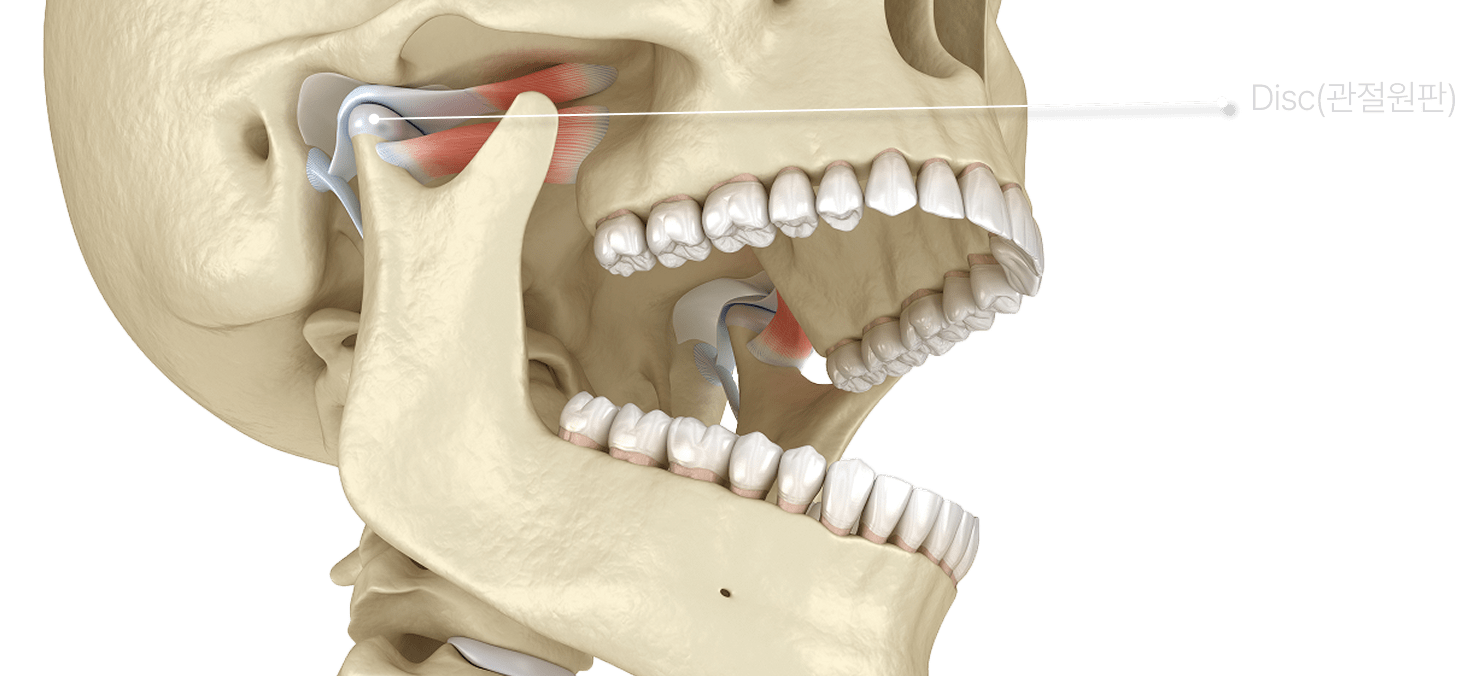

수턱 주변의 심부 근육의 긴장, 턱관절을 형성하는 조직의

염증성 상태가 턱관절 장애를 유발합니다.

턱관절장애는 턱을 움직일 때 통증, '딱' 소리, 개구 제한 등이

나타나는 기능성 장애입니다. 일상 속에서는 씹기 힘듦, 턱 피로감,

입이 잘 안 벌어지는 느낌으로 불편을 겪게 됩니다.